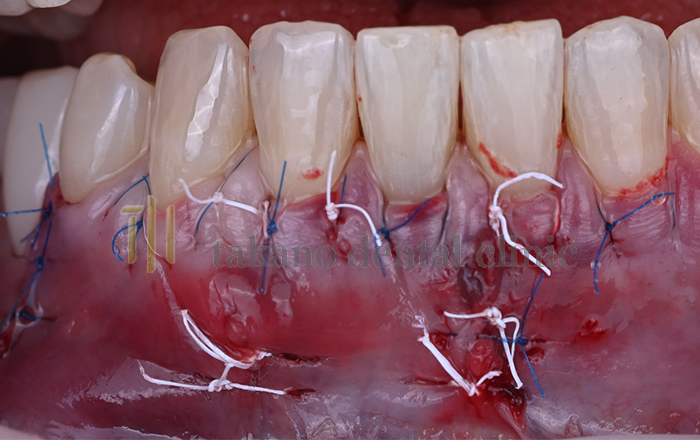

下がった歯ぐきを治療するためには歯周形成外科治療が必要になります下がった歯ぐきを治療するためには歯周形成外科治療が必要になります。外科治療には遊離歯肉移植術、結合組織移植術、歯肉弁歯冠側移動術といった手術をおこないます。

結合組織移植術

どのような場合の治療法か

ほぼ全てのケースで行うことができます。上あごから結合組織(歯ぐき)を採取して移植するので取れる歯ぐきの量によっては1度で全てを治療できないことがあります。その場合歯ぐきが再生するのを待って何度か手術を行うことで改善していきます。

遊離歯肉移動術

• 術中

治療例